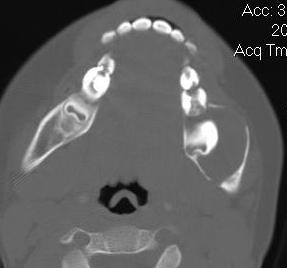

Cyst Associated with an Impacted Tooth in a Child

• Cysts either developmental or of unique dental tissue origin

• Tumors